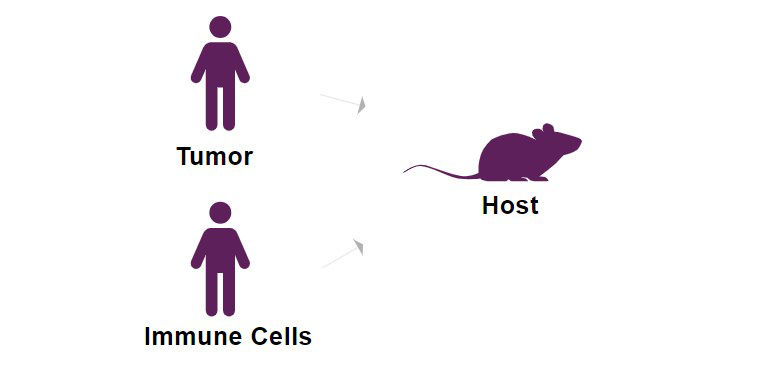

NOG-EXL mouse model from Taconic outperforms NSG-SGM3 in new

NOG-EXL mouse model from Taconic outperforms NSG-SGM3 in new

NOG-EXL mouse model from Taconic outperforms NSG-SGM3 in new,

NOG-EXL mouse model from Taconic outperforms NSG-SGM3 in new, NOG-EXL mouse model from Taconic outperforms NSG-SGM3 in new,

NOG-EXL mouse model from Taconic outperforms NSG-SGM3 in new, CIEA NOG mouse® | Taconic Biosciences,

NOG-EXL mouse model from Taconic outperforms NSG-SGM3 in new, NOG Portfolio Mouse Strains for Oncology & Immuno-Oncology,